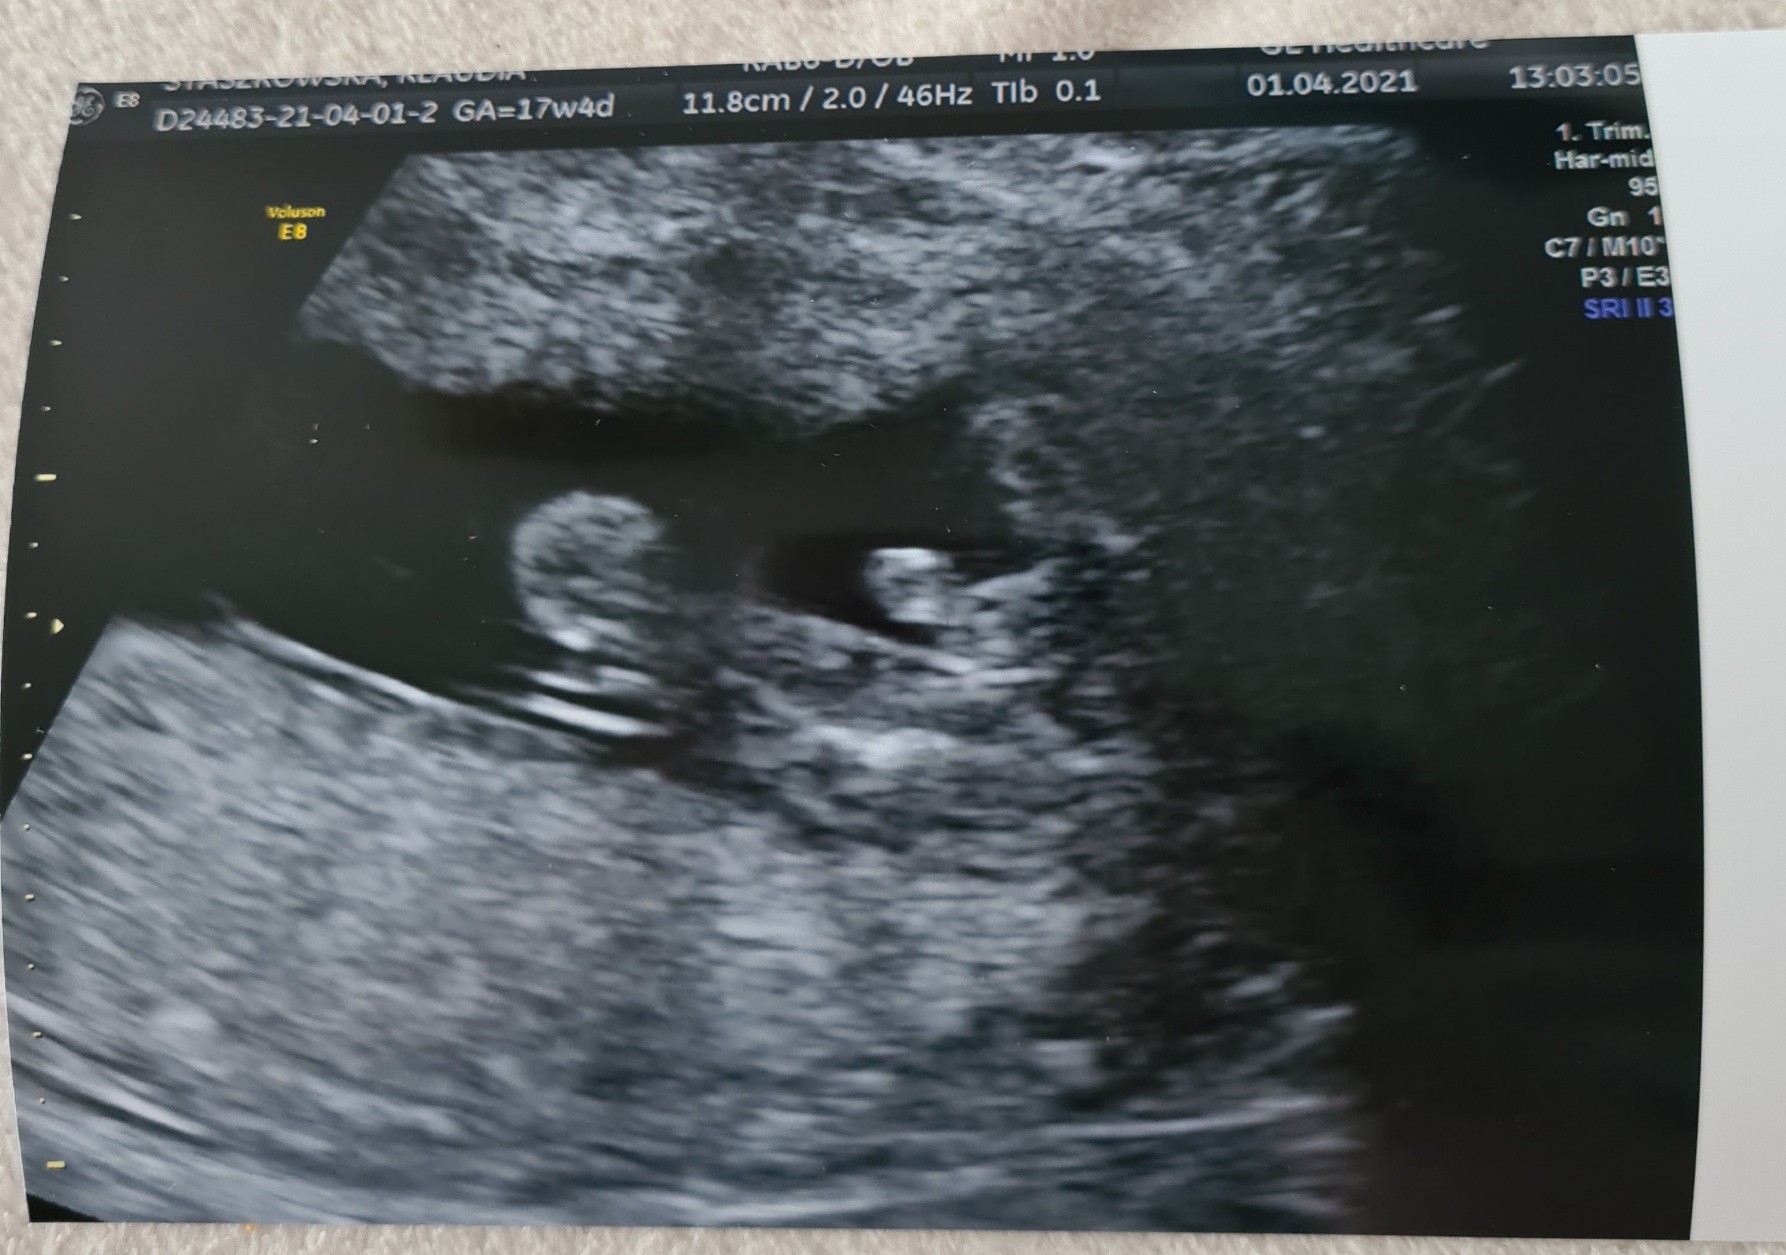

Usg 17+4

Jak myślicie? Lekarz mówi, że chłopak bo widać jąderka. Ale wiem ,że lekarz może się pomylić. Macie podobne zdjęcia? :)